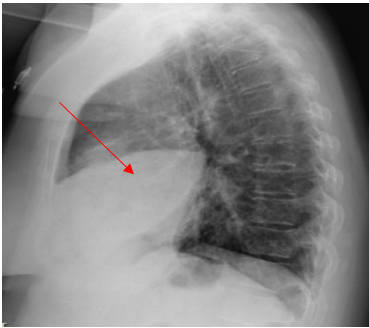

A 52-year-old Caucasian female, who is a resident of southwestern Ohio, presented to the emergency room with a chief complaint of a two-week history of right-sided chest pain, which had progressively worsened despite two courses of antibiotics and pain medications following her two recent visits to the emergency department. She also described subjective fever, shortness of breath, nonproductive cough and weight loss of 4 kg over the last two weeks. She was a smoker of ½ pack per day for 20 years and quit smoking 4 weeks ago. The patient’s past medical history includes anxiety, depression, gastroesophageal reflux disease, hypertension, mitral valve prolapse, and migraine headache. Her chest pain started in early September, and it was described as stabbing and pleuritic, which was also noted to be reproducible to palpation of the chest wall. She was seen first at the emergency department two weeks prior to the current presentation for evaluation of the right-sided chest pain. Still, at that time, there was no fever or cough, and her vitals were stable with Oxygen Saturation 94% on room air, although her laboratory testing was significant for leukocytosis with (WBC):16.6 K/UL with 68.5% neutrophils. Chest-X-ray demonstrated an infiltrate in the right lung base medially, while CT–chest angiography demonstrated no evidence of pulmonary embolism and right middle lobe consolidation consistent with pneumonia. There was no mediastinal or hilar lymphadenopathy, (Figures 1 and 2).

Figure 2. CT-chest angiography showing right middle lobe consolidation.